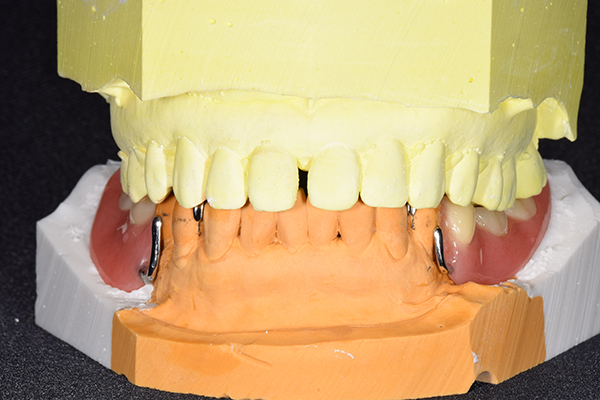

6.噛み合わせチェック

噛み合わせチェックでは、型取りした模型で、写真のようなワックスをのせた入れ歯の前段階のものを使用していきます。前の入れ歯がある場合は、そちらも参考にしながらチェックしていきます。 しゃべりやすさも考慮した上で入れ歯の噛み合わせの高さを決定していきます。 この時にフェイスボウという、上顎と頭の位置を精密にみていくための装置を使用することもあります。

7.歯を並べる

噛み合わせをが決定したら、咬合器という装置に模型をくっつけて、歯を並べていきます。自費の入れ歯の場合こちらを歯科医師で行います。保険の入れ歯の場合は模型を技工所に送り、技工士さんに歯を並べてもらいます。最終的な入れ歯を作る気持ちで並べていきますが、どうしても噛み合わせの誤差が模型とお口の中とでは生じてしまいますので、歯をならべたものを患者様のお口の中にいれて確認していきます。

確認することとしては、歯と患者様のお顔の調和、噛み合わせ、見た目、フィット感などです。 こうすることで、患者様に合った精密な入れ歯を作ることができます。

8.患者様のお口に入れて修正

この写真は、実際にお口の中にいれてみて、噛み合わせのチェックを行い、調整したものになります。 上下の入れ歯で青い点、赤い点がはっきりあり、これはしっかり奥歯で噛めるというサインになります。 また、入れ歯自体の大きさや、違和感が強くないか、お顔と調和しているか、唇との関係などをみていきます。もし、ここで大きな修正が発生する場合はもう一度お時間をもらって次回再度確認させて頂きます。 これで修正が終わったら、その模型を技工所に送り、入れ歯を完成させてもらいます。